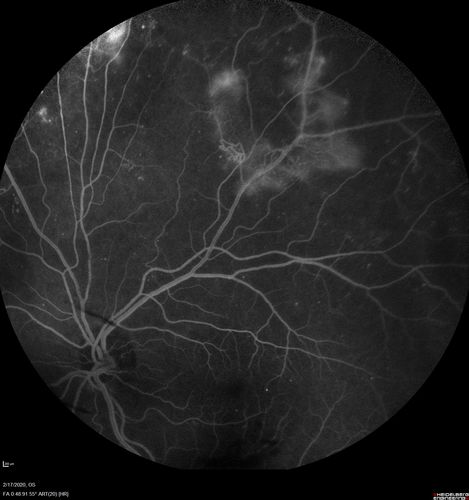

PDR and Vitreous Hemorrhage - High Risk Left Eye - Low Risk Right Eye

50 year old man with type I diabetes mellitus for 26 years. New Vitreous Hemorrhage in the left eye. Both eyes have NVE. Both also have foveal hypoplasia

Vitreous Hemorrhage and Proliferative Diabetic Retinopathy - Low risk right eye - High Risk Left Eye - Also Fovea Plana